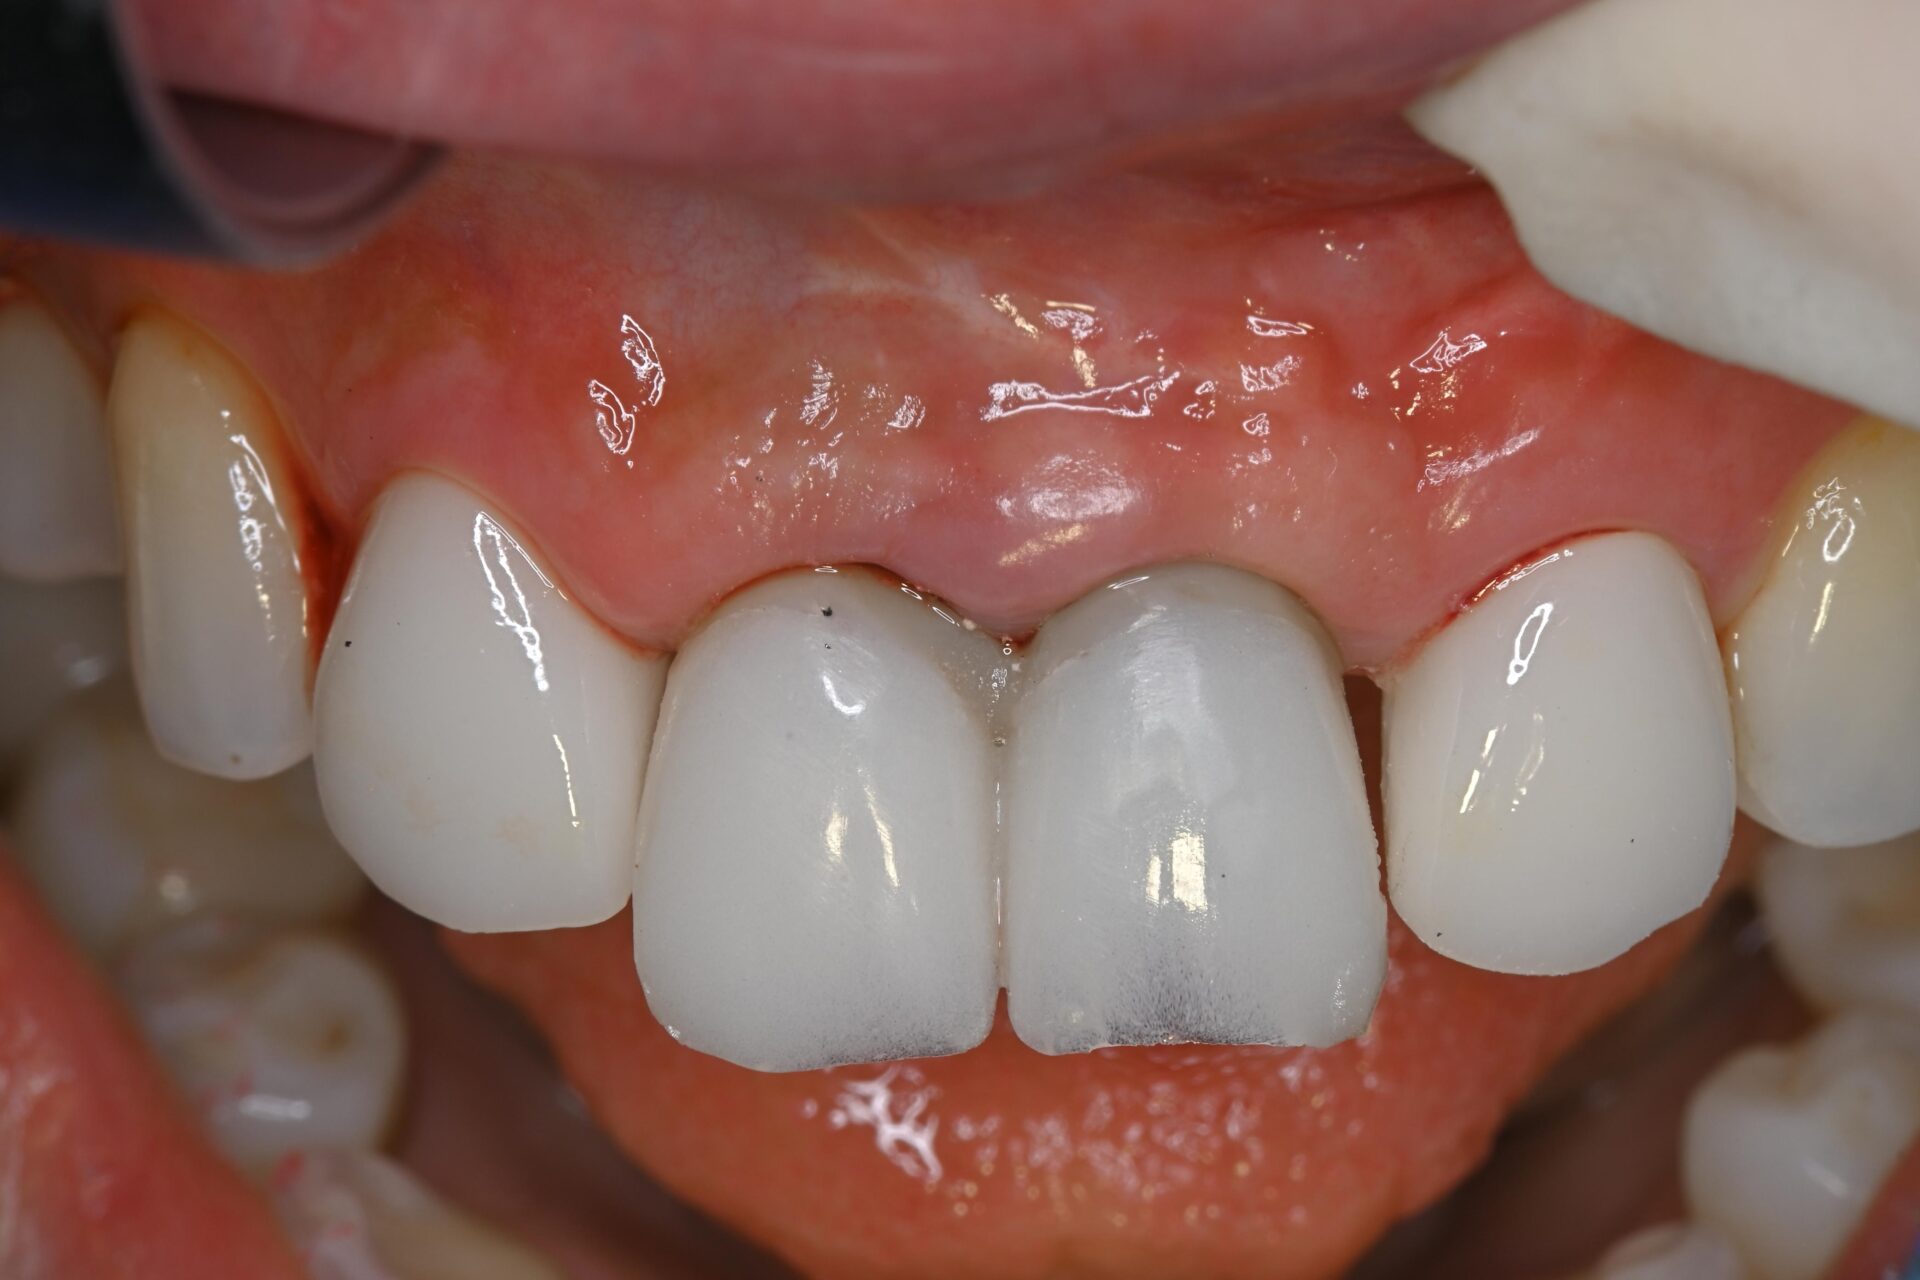

プロビジョナルレストレーションの装着

インプラント体を埋入したその日のうちに仮歯を装着。審美性を確保すると同時に、歯肉の形態を整える役割も担います。患者さんは治療当日から自然な見た目と会話・咀嚼機能を取り戻すことができました。